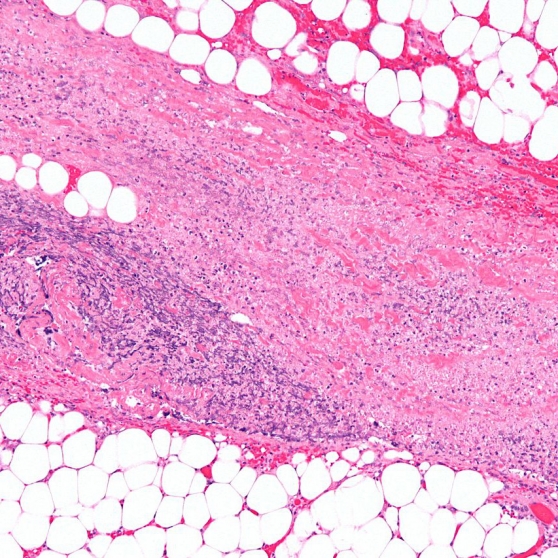

Necrotizing fasciitis is a rare but serious bacterial infection of the skin and fascia. The infection is contracted through an external injury and has early flu-like symptoms. The bacteria can spread quickly and attacks the surrounding tissue, causing it to die. If not treated, the infection can lead to organ failure and death.